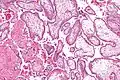

Micrografía que muestra vellosidades coriónicas. Ampliación muy alta. Tinción H&E.